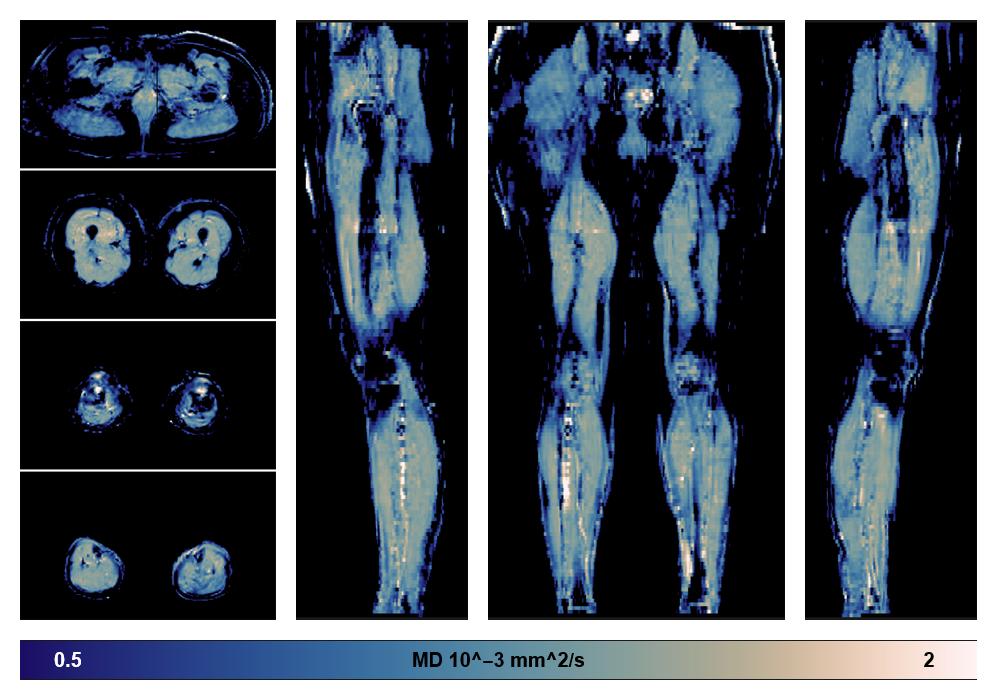

• Mean diffusivity

IVIM corrected whole leg muscle mean diffusivity obtained from diffusion tensor imaging.